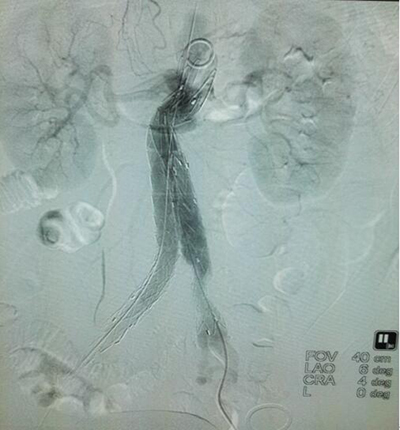

(手术过程简要步骤图)

A经两侧股动脉进行插管,并将导管置入股动脉。

B支架血管的主体沿着导管,由右侧置入主动脉。

C支架血管主体张开固定,并将对侧脚支架经血管置入主体中与主体支架血管脚充分贴合,形成一个“人”字形的整体结构。

D对侧脚支架在血管内张开固定,达到完全阻隔血液及压力传入动脉瘤中,最终避免了血管破裂的发生。

(患者杨某术中置入导管、成功放置支架影像图)

在整个手术过程中除了正常的观察患者的生命体征变化之外,该患者因年龄大、术前检查显示有高血压、冠心病、陈旧性心梗等疾病,无疑为手术的开展又增加了难度和风险。在术前充足准备的保驾护航下,马建仓教授运用娴熟的技术操作,带领团队突破重重困难,安全顺利的为患者实施了手术,手术过程顺利,前后总耗时90分钟,为患者成功的解除了“定时炸弹”般的危险。术后患者自我感觉良好,手术后的创伤只有1-2厘米大的穿刺点,患者术后很快就恢复了正常的生活,经过一系列的治疗和精心的护理患者已经康复出院,住院周期仅仅只有4天。